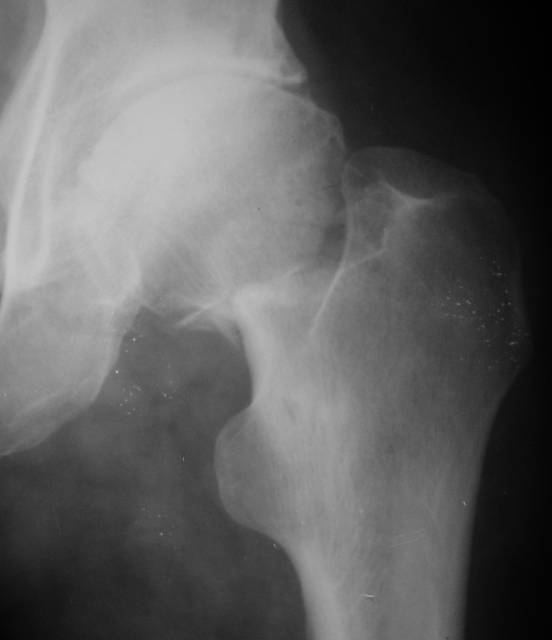

Насчет 8 см согласен с А.Н. Челноковым, это наверное ортопедическое за счет приводящей, сгибательной контрактуры и, возможно, колена. на ликвидацию укорочения у нас обычно уходит около 2-х нед. снимки в приложении, возможно не очень показательные, но других с ходу не нашел, завтра еще поищу.

Еще пара фото, ситуация несколько иная, задачи те же, открытое вправление застарелого вывиха в 2002, молодой возраст. Сейчас госпитализирована для эндопротезирования.

AV> опираясь на стул. На ногу не наступает. Укорочение 8 см. Иногда

А за счет чего такое укорочение? По снимку не видно соответствующего дефекта. Ну плюс приводящая контрактура - но все равно как-то уж больно много. Может, сделать снимки и таза обзорный с обоими проксимальными отделами бедра, и коенный суставов с приложенной линейкой какой?

Судя по снимку, максимум истинное укорочение около 4 см, что может быть коррегировано интраоперационно. Вопрос в другом: куда ставить ацетабулярный компонент в истинную или во вновь сформированную ( впадина диспластичная).

The X ray that you provided does not show 8 cm of shortening. Perhaps you could send one showing the whole pelvis and proximal femurs.

I agree with Dr Eid's comments. The origin of the 8 cm leg length difference is a puzzle. Is this a clinical measurement? In that case contracture of the joint might affect the measurement. Can we see an AP pelvis to include both hip joints (including a calibration object with a known length) so that the difference in leg lengths that can be ascribed to the hip deformity and bony reabsorption can be measured. This sort of xray will help with templating for the TJR also. I would be very tempted to do a one stage procedure and accept some shortening. Shoe lifts should take care of a 3-4 cm difference.

До травмы проблем с ногой не было. Укорочения, болей и т.п. не отмечал. Сегодня перемерял укорочение - меньше 7 см намерять не

По уровню малых вертелов (с учетом рентгеновского увеличения) получается 5 см. Клинически ногу низвести путем тракции невозможно. Из движений - сгибание до 40*, остальные движения "символические".

Ортопедическое укорочение пострадавшей ноги может быть и 7, и 10 см. за счет контрактур в тазобедренном суставе, а вот истинное укорочение, судя по представленным рентгенограммам, вряд ли больше 4 см.